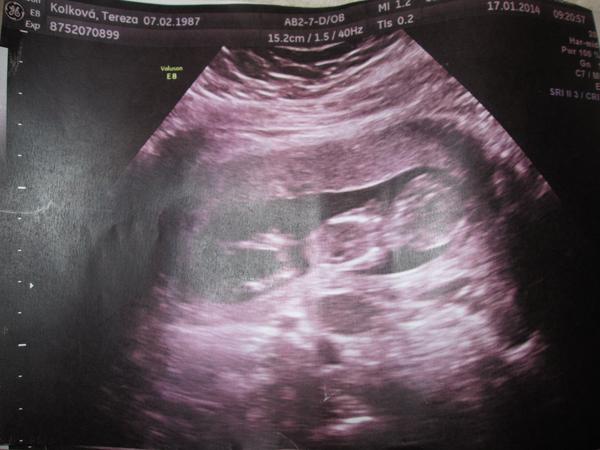

Je to holčička nebo chlapeček? Foto ultrazvuku

Ano,správně ☺je tady spousta fotek kde je jen hlavička a kousek bříška,tak jsem taky podobné přidala 😉 bohužel nám paní doktorka neudělala fotku nožiček...

Na UZ ve 14 tt nam rekli na 100% kluk a ted ve 22 tt, ze si neni jisty😳samozrejme je nam uplne jedno co to bude😍 ja za sebe tam vidim kavove zrno😊

No já vidím opravdu jasnou holčičku 🙂 tady snad nekdo o zom pochybuje,mam 3syny a obrázky jsem měla jiné relax85,nvo jineho by bylo kdyby nebyly nozicky takhle od sebe,kdyby to byl klučík,tak by výrazně čouhalo něco dopředu , ;) 🙂